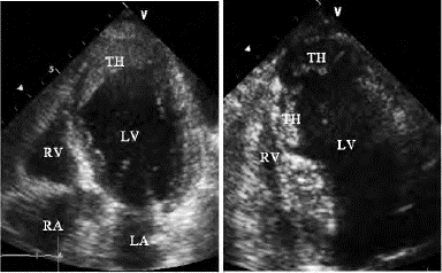

(1)二、三尖瓣断裂的乳头肌连于腱索,随心动周期往返运动,收缩期进入心房,舒张期回到心室(图19-13)。

图19-13 乳头肌断裂二维超声心动图

左图心尖四腔切面显示前外乳头肌断裂,舒张期两断端均位于左室内;右图则显示收缩期断裂部分的乳头肌随腱索甩入左房,并致二尖瓣明显关闭不全,图中箭头所指为乳头肌的两个断端